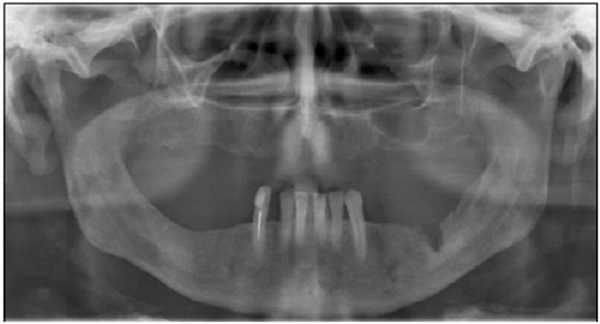

Лучевой остеонекроз представляет собой гибель костной ткани и является наиболее тяжелым последствием лучевой терапии онкологических заболеваний головы и шеи. В нашем случае 7 (9,3%) пациентов группы контроля обратились с жалобами на боли и длительное незаживление лунок после удаления зубов. Удаления были произведены в стоматологических учреждениях города в сроки от 7 до 12 мес после окончания лучевой терапии. Во всех случаях был выставлен диагноз «остеорадионекроз» (рис. 3). Рисунок 3. Остеорадионекроз. Во всех случаях остеорадионекроз характеризовался длительным течением, с периодами обострения и отсутствием четко определяемых границ демаркации секвестра. Хирургическое вмешательство в основном было направлено на предупреждение развития абсцессов и флегмон ЧЛО. В одном случае течение радионекроза сочеталось с одновременным рецидивом опухоли.